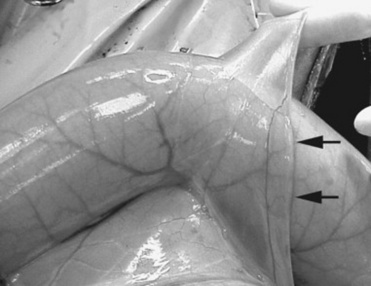

The initial response to serosal injury has been studied in laboratory animals using predominantly scarification of organs or fecal contamination of the peritoneal surface. The response to ischemia or distention of the equine small intestine is similar, though often more severe. During ischemia the mesothelium is rapidly lost, with subsequent serosal swelling with edema. During reperfusion the serosal vasculature becomes more permeable, and polymorphonuclear cells and mononuclear cells migrate through capillaries or venules and infiltrate into the serosal connective tissue layer. Neutrophils accumulate at the basement membrane around vessels and within lymphatics. Fibrin accumulates within the serosa and on the surface. WBCs release oxygen radicals and proteolytic enzymes, resulting in disruption of collagen, the primary ground substance of the serosa. The denuded serosal response includes increased vascular permeability, which allows the surface to be covered with a fibrin clot. After 24 to 48 hours there is massive accumulation of cells, which are predominately neutrophils, within the serosa and at the new surface.

In the horse the serosal injury is frequently caused by bowel distention. The cellular injury is similar to an inflammatory model except for the vascular sequelae. After small intestinal ischemia there is an initial vascular hyperemia in most of the bowel but a reduction of perfusion to the serosa.231 This same effect occurs during bowel distention and is even greater after alleviation of distention. The edema formation in distended bowel takes place immediately and increases serosal tissue pressure, which exerts extravascular pressure and closes capillaries and venules.231 This continues after bowel decompression, resulting in ischemic injury during reperfusion of the serosa. Reperfusion after decreasing bowel distention also causes serosal endothelial cell swelling and capillary plugging. This helps to explain the adhesions seen in bowel that was distended only proximal to an obstruction or strangulating lesion but was otherwise not involved in an ischemic lesion.